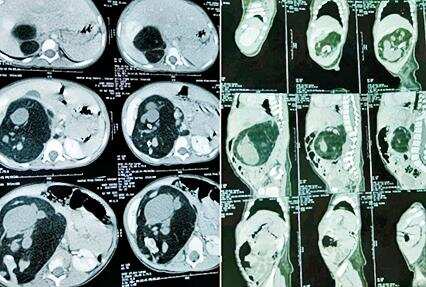

AHMEDABAD: An 18-month-old girl from Neemuch in Madhya Pradesh was brought to Civil Hospital for an unusual trouble – the girl had a swelling in her stomach, which turned out to be a fetus! In medical parlance, it was a rare case of fetus-in-fetu where one of the twins in the uterus is malformed and parasitic in nature and grows in another twin’s body.

Dr Rakesh Joshi, professor and head of the pediatric surgery department at Civil Hospital, said that Vidhi (name changed) is daughter of a jewellery shop owner. “The couple had got worried due to the swelling of her stomach. The CT scan revealed presence of the foetus. They went to hospitals and Rajasthan and Madhya Pradesh but without success,” he said.

The foetus had formative brain and vertebral column, they added. “Fetus-in-fetu is a rare congenital abnormality having a prevalence of about one in 5 lakh live births. Across the world, there might be about 200 cases reported in literature. For us, it is the third such cases in over two decades,” said Dr Joshi.